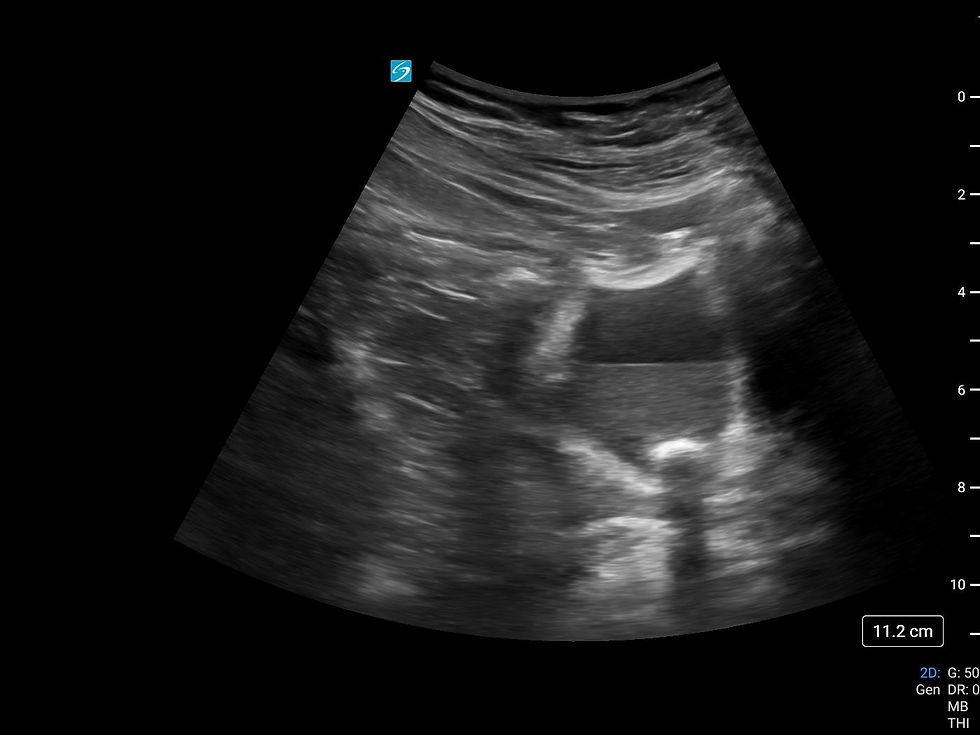

Patiente se présentant pour deg, asthénie, anorexie, vomissement. Trouvaille d'une créatinine de novo à 650. Pas IECA/AINS. Un peu intense pour de la déshydration... Ma collègue à donc décidé de prendre la machine d'écho.

Vue à droite :

Vue à gauche :

Hydronéphrose modéré-sévère bilatérale! Et hop... uro immédiatement consulté... patient envoyé dans l'uroscan suivi de la pose rapide de JJ avec une excellente évolution! Tsé, quand l'écho change la donne!